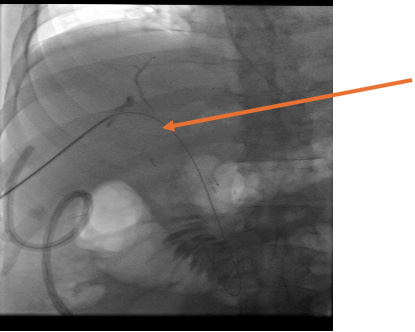

Our patient is a 59-year-old Caucasian male with medical history significant for hypertension, coronary artery disease, obesity with a body mass index of 38, and prior cholecystectomy, who was referred to The University of Kansas Hospital for obstructive jaundice. Here, he was appropriately evaluated by GI with endovascular ultrasound and biopsy. A diagnosis of cholangiocarcinoma was made, and he was referred to HPB surgery. Due to complete obstruction of the common bile duct, GI was unable to place a biliary stent. Alternatively, he underwent PTC with biliary drain placement with IR prior to surgery (Image 1).